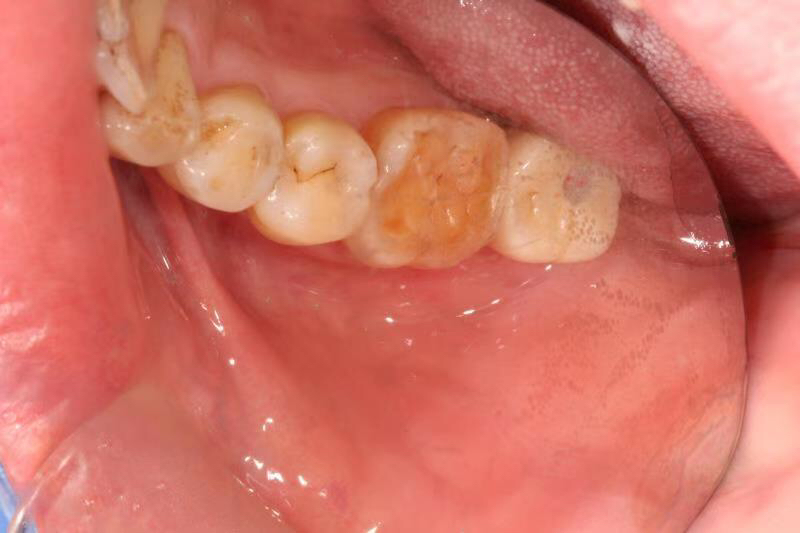

患者中年男性,右下7号牙龋坏未及时处理至残根无法修复,CT检查发现骨量尚可,可以即拔即种,并且不需要植骨,节省了患者治疗周期,整个治疗过程用了4个月患者就戴上了牙齿。